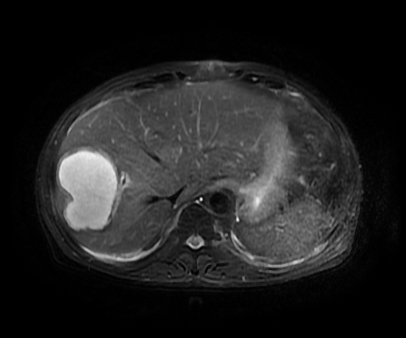

手术前

今年春节过后,老杨身体一直不舒服,乏力伴有发烧二十多天,他却不以为意,以为糖尿病老毛病犯了,在家多睡睡觉休息就好了。后来实在熬不住了,好友闻讯后劝他来康华医院检查治疗,原本以为只是单纯的糖尿病,不曾想B超检查发现右肝上有一个10余厘米的巨大包块,考虑肝脓肿。经肿瘤科会诊后确诊为肝脓肿,建议CT引导下行经皮肝穿刺引流术(PTCD)。因脓肿较大若不手术,脓肿有自行破裂的风险,届时将造成腹腔大面积感染及脓毒血症,甚至危及生命。随即病人就转至肿瘤科。

经过完善的术前检查,以及肿瘤科、内分泌科等专家的会诊后,患者于3月中旬进行手术。在64排128层CT的引导下,病灶得以精准定位并引流,在肿瘤科王剑飞主任、主治医师黄忠炎以及放射科医师的娴熟配合下手术很顺利,当即引流出脓液230ml左右,病灶明显缩小。